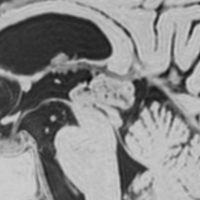

これも偶然発見された無症状の女性の小さい松果体細胞腫ですが,ほとんど実質性でのう胞がありません。右はCISSという画像です。中脳の視蓋は圧迫されて変形していますが,中脳水道がまだ閉塞していないのがよくわかります。

左側はMRI血管像です。赤く塗った松果体腫瘍がたくさんの血管とくに静脈に囲まれていて深い位置にあるのがわかります。右は手術後のMRIです。幸い後交連というところも残せたので眼球運動障害(ものが2重に見える)という後遺症は出ませんでした。